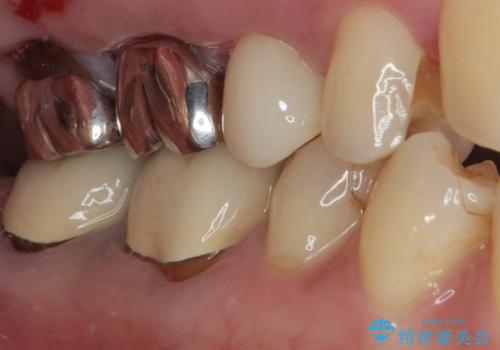

歯の形態や咬み合わせが正確に反映されるように、シリコーンゴムによる精密な型どりを行いました。

完成したセラミックインレーは精度が高く、適合性に優れているため、歯と調和した自然な仕上がりとなります。